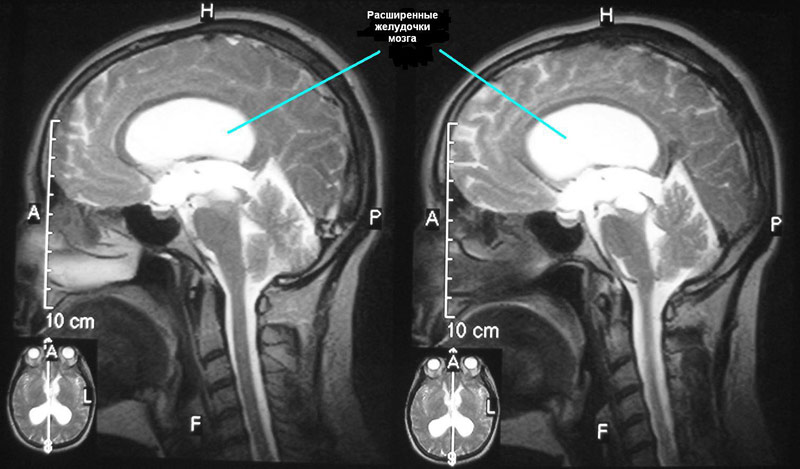

Гидроцефалия – заболевание, для которого характерно излишнее скопление жидкости в желудочковой системе мозга. Явление, при котором возникают затруднения ее движения от места секреции к субарахноидальному пространству, называют окклюзионной гидроцефалией.

Если скопление жидкости происходит из-за нарушения абсорбции ликвора в кровеносную систему, то такую патологию называют арезорбтивной гидроцефалией.

Водянка мозга может быть врожденной или приобретенной. Врожденная форма заболевания обнаруживается, как правило, в детском возрасте. Причинами приобретенной формы гидроцефалии зачастую становятся инфекционные процессы (например, менингит, энцефалит, вентрикулит), новообразования, сосудистые патологии, травмы и пороки развития.

Водянка может возникнуть в любом возрасте. Это состояние опасно для здоровья и требует немедленного лечения.